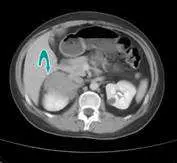

本題為反向題(問「最不可能」)的延伸題,接續上題情境:30歲女性出現聲音變粗、陰蒂增大等男性化(virilization)表現,電腦斷層(CT)顯示腎上腺區域病灶,血液檢驗 Testosterone 為 250 ng/dL、DHEAS(dehydroepiandrosterone sulfate,脫氫異雄固酮硫酸鹽)為 800 µg/dL。本題要求根據影像與賀爾蒙數值判斷最可能的診斷。

影像分析:

電腦斷層兩張橫切面影像均可見腎上腺區域(右側腎上腺附近)有以青色箭頭標示的軟組織密度腫塊,與正常腎上腺形態不符,提示為腎上腺佔位性病灶(adrenal mass)。

- 第一張影像:顯示上腹部橫切面,可見右腎上腺區域有界限清楚之腫塊,周圍結構受壓但無明顯鄰近器官侵犯表現。

- 第二張影像:另一層面顯示同一腫塊延伸範圍,腫塊為均勻密度,邊界尚清,影像特徵符合腎上腺功能性腺瘤(adrenal functional adenoma)或腎上腺皮質癌(adrenal cortical carcinoma)。

影像加上賀爾蒙數值(DHEAS 顯著升高至 800 µg/dL),共同指向腎上腺來源之高雄激素血症。